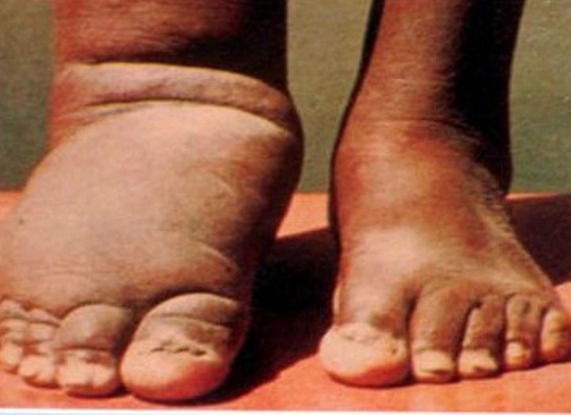

राप्ती गाउँपालिका स्वास्थ्य शाखाका प्रमुख नारायण राउतले विगत वर्ष जस्तै यस वर्ष पनि नागरिकलाई हात्तीपाइले रोगबाट बचाउन औषधि खुवाउन थालिएको जानकारी दिए। क्युलेक्स वा एनोफिलिसको पोथी लामखुट्टेको टोकाइबाट फाइलेरिया नामक परजीबीबाट सर्ने यो रोग शरीर कुनै एक भाग वा अङ्गमा लाग्ने र त्यो अङ्ग सुनिँदै जाने भएकोले हात्तीपाइले रोग भनेर चिनिन्छ

“लामखुट्टेको टोकाइबाट सर्ने रोग विभिन्न खालका छन् तर पनि हात्तीपाइले रोग नसर्ने रोग हो, यसले मानिसको तुरुन्तै मृत्यु हुँदैन,”उनले भने, “यस रोगले भेटेपछि उपचार नहुने भएकाले मानिसलाई जीवनभर भद्दा शरीर लिएर बाँच्नुपर्ने बनाउँछ । ”लामखुट्टेले रातको समयमा रोगीलाई टोक्दा रगतसँगै सुक्ष्म फाइलेरिया यसको पेटमा जान्छ । लामखुट्टेको पेटमा विकसित भएर यो परजीवी मुखको ¥याल ग्रन्थीमा जम्मा हुन्छ ।”

हात्तीपाइले रोग क्युलेक्स प्रजातिको लामखुट्टेको टोकाइबाट लाग्ने गर्दछ । यो रोग लागेको ६ देखि १० वर्षपछि मात्रै शरीरको बाहिरी भागमा देखापर्ने भएकाले रोगलाग्नु भन्दा अघि नै औषधि सेवन गर्नुपर्ने चिकित्सकको सुझाव छ ।

भारतीय उपमहाद्वीपको धेरै पुरानो रोग हो । यो एक पटक लागेपछि जीवनभर निको हुँदैन । मानिसको शरीरमा हात्तीपाइले रोगको परजीवी प्रवेश गर्नासाथ यो रोग देखापर्दैन । यो परजीवी करीब छ वर्षसम्म मानिसको शरीरमा सुसुप्त अवस्थामा रहन्छ । यो परजीवी शरीरमा रहे हात्तीपाइलेको औषधि सेवन गरेपछि कसै कसैलाई ज्वरो आउने, वाकवाकी लाग्ने, वान्ता हुने जस्ता सामान्य असर देखापर्न सक्ने छलफलमा जानकारी गराइएको थियो । रासस